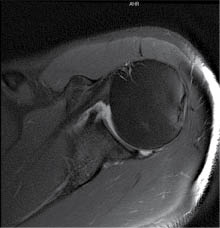

Imagen: se realizó una radiografía con proyección anteroposterior (Figura 1), y una resonancia magnética simple de hombro izquierdo (Figuras 2 y 3) y se realizó el diagnóstico de luxación glenohumeral, inestabilidad anterior de hombro, lesión de Bankart y lesión de Hill-Sachs.

En las imágenes tomadas antes del procedimiento quirúrgico se observa, en la primera radiografía simple de hombro izquierdo en proyección anteroposterior, una luxación de la articulación glenohumeral, mientras que en la resonancia magnética simple (cortes axial y coronal), se detecta una lesión de Hill-Sachs y una lesión de Bankart, las cuales de acuerdo con la literatura son característica en los pacientes con luxación glenohumeral e inestabilidad anterior de hombro.

Figura 3